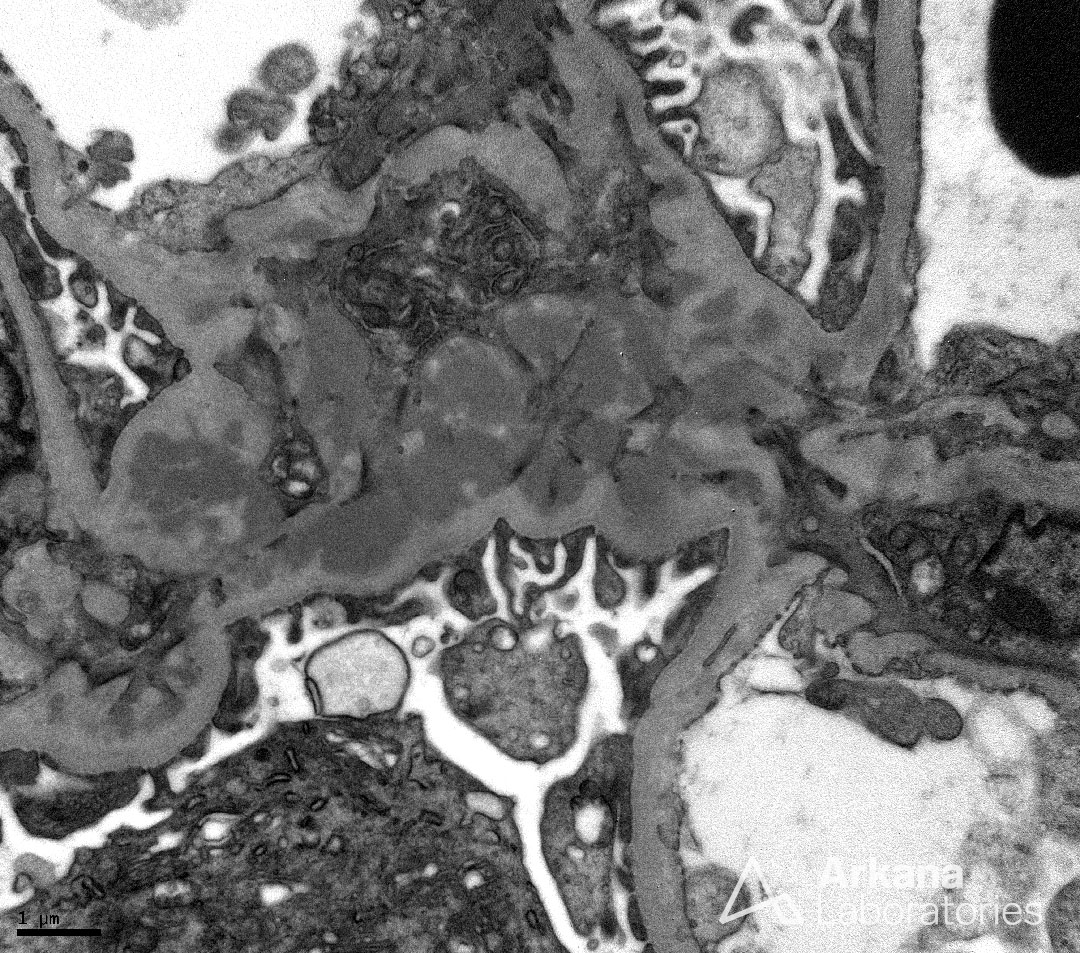

Mesangial Immune Complex Deposits in IgA Nephropathy_3